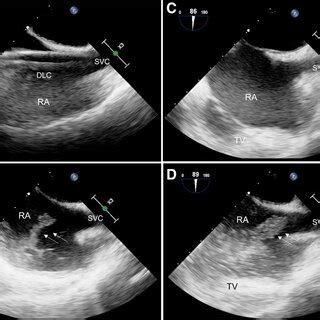

Hey guys! Ever wondered how those crystal-clear images of your heart’s big veins are captured during an echocardiogram? Well, it all boils down to the bicaval view echo probe position . This is super important for cardiologists and sonographers to accurately diagnose and understand what’s happening inside the heart. Getting this position right allows us to visualize the superior and inferior vena cava (the big veins bringing blood back to the heart) and the right atrium, giving a comprehensive view of the heart’s function. Let’s dive deep into how to nail this position and get those perfect images! This is critical for assessing right heart function, detecting issues like thrombus (blood clots), and measuring the size and function of the vena cava. Accurate probe placement is key to getting these measurements right and making sure patients get the best care.

So, why is this bicaval view so crucial? Think of the heart as a bustling city, and the vena cava are the highways bringing in all the traffic (blood) from the rest of the body. The bicaval view gives us a panoramic view of these highways as they enter the heart’s main station (the right atrium). This view is your go-to for checking the size and shape of these major vessels and how they function. This is especially vital when checking for clots, which can be deadly. It also helps in assessing the pressure within the right atrium, a key indicator of heart health. Furthermore, it gives a good look at the tricuspid valve, ensuring it’s working properly. This view is also super helpful in assessing patients with shortness of breath, chest pain or other symptoms related to heart problems, the bicaval view can provide crucial insights.

Now, let’s get into the nitty-gritty of how to get the perfect view. First, remember the patient should be lying on their left side, which is known as the left lateral decubitus position. This helps bring the heart closer to the chest wall. The probe itself is the magic wand, and the specific type you use (usually a phased array) is designed for this kind of imaging. Then comes the tricky part: the probe position. Imagine you are trying to catch the sun at the optimal angle. The goal is to position the probe under the sternum (the breastbone), aiming slightly towards the patient’s right shoulder. The idea is to align the ultrasound beam with the vena cava so you can see them clearly as they enter the right atrium. Be patient and adjust slightly until you get the best image. The orientation marker on the probe is your best friend here; it should point toward the patient’s right. It may take some practice, but you’ll get the hang of it.

Alright, let’s break down the process step-by-step for the bicaval view echo probe position . First, you’ll need the right equipment: an ultrasound machine, the right kind of probe (usually a phased array), and some acoustic gel (that stuff that makes everything glide smoothly). The patient should be positioned in the left lateral decubitus position. This positioning moves the heart closer to the chest wall, making it easier to get clear images. Now, apply the acoustic gel liberally to the probe head. This helps eliminate air pockets and ensures good contact with the skin. Place the probe just below the sternum, aiming towards the patient’s right shoulder. Gently angle the probe and try to visualize the right atrium and the vena cava. Remember to keep the probe flat against the chest wall to get the best contact and minimize any loss of image quality. Slight adjustments are often necessary to find the sweet spot, the one where the images are super clear. Scan through the various angles to see which one gives you the best picture of the superior and inferior vena cava entering the right atrium.